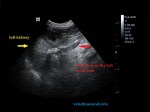

She has been diagnosed with adrenal-dependent Cushing’s disease 4 months ago. The left adrenal gland was found enlarged and there were calcifications on its caudal pole. After undergoing treatment with Vetoryl (trilostane) the clinical symptoms subsided. The owner noticed increased thirst (polydipsia) and the resultant increased urination (polyuria) over the last week. Abdominal pain and recurrent vomiting were reported by the owner during the last 3 days.

- Infiltration of the liver and presence of subcapsular hematoma.

- Infiltration of the caudal vena cava by the adrenal gland, which had infiltrated all the surrounding tissues.

- Thromboses were present on the right and left renal vein due to stenosis of the caudal vena cava.

Infiltration of the caudal vena cava caused by the left adrenal gland mass, thromboses of the right and left renal veins, lesions potentially metastatic in the liver and clinical manifestation of pancreatitis probably induced by high levels of corticosteroids.